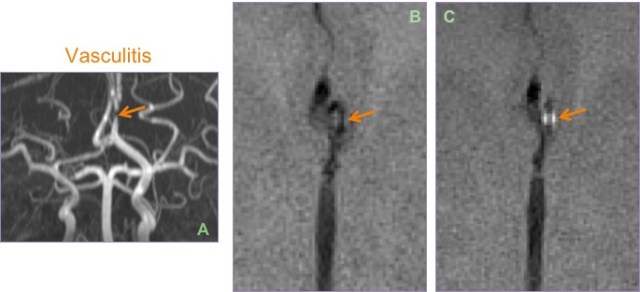

DSA (A & D) and MIP images from CTA brain (B & C) show multifocal short segment stenosis of medium-sized intracranial arteries of the anterior and posterior circulation.

Leptomeningeal biopsy showed vasculocentric transmural inflammation of the small arterioles with fibrinoid necrosis, consistent with vasculitis.

Vessel wall imaging may be performed in this case to look for homogeneous circumferential wall enhancement.

Biopsy proven case of CNS vasculitis. Severe focal stenosis of the left A2 segment noted on the MIP-MRA (A); enhancement of the stenosed sesgment is seen after contrast administration on post VW image (C). Pre (B) image is shown for comparison.